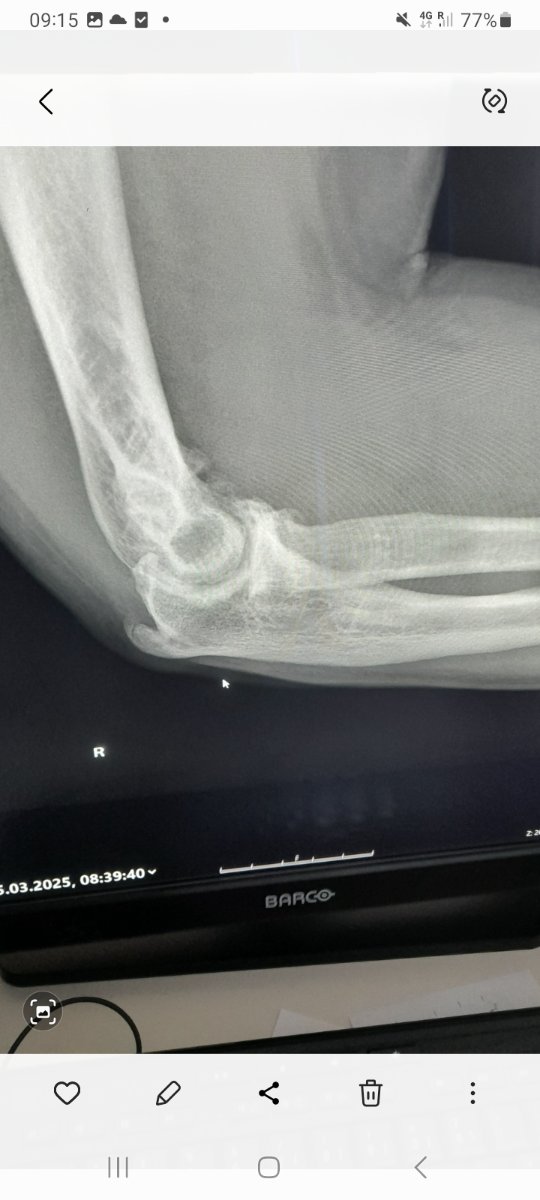

Inderdaad geen onverwacht nieuws...het is wat het is...ik wilde enkel een bevestiging hebben wat de oorzaak is waarom ik mijn rechterelleboog niet meer volledig kan strekken en die heb ik nu 🤭Klote allemaal René!, maar geheel onverwacht nieuws is het niet lijkt mij.....